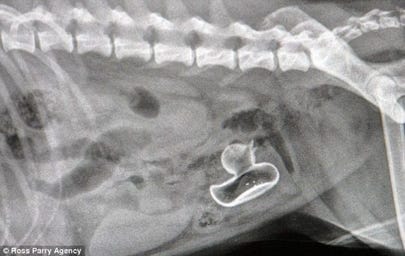

In X-rays

I see your pregnant dog xray and raise you a rubber ducky dog xray : pics